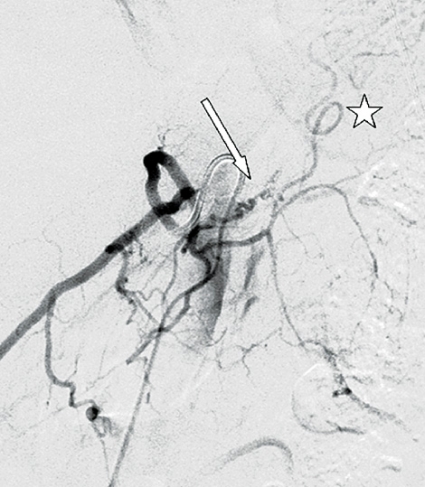

Ånyo gjordes en akut MRT inklusive spinal kontrastförstärkt MR-angiografi som påvisade en spinal dural arteriovenös fistel i nivå med Th11. En diagnostisk konventionell spinal angiografi verifierade diagnosen, och i samma seans kunde fisteln behandlas endovaskulärt utan komplikationer (Figur 2). Patienten överfördes till vårdavdelning, där man redan några dagar efter behandlingen noterade en påtaglig regress av samtliga symtom: han klarade då att stå och gå – dock med gåbord. Vid klinisk kontroll efter sex månader kunde patienten gå obehindrat och uppvisade nästan fullständig regress av övriga symtom. Han hade även bibehållen erektionsförmåga.

Om möjligt görs detta i samband med den diagnostiska angiografin, genom mikrokateterisering av fisteln med efterföljande embolisering med polymer eller annat permanent emboliseringmaterial [4]. Målet är att emboliseringsmaterialet ska passera från artärsidan genom fisteln och vidare ut i den dränerande venen och täppa till denna. Vid kirurgisk behandling görs en laminektomi eller hemilaminektomi på den aktuella nivån, varefter duran öppnas och venen delas. Att sluta den dränerande radikulomedullära venen är således det avgörande behandlingsmomentet vare sig patienten behandlas endovaskulärt eller med öppen kirurgi [9].

Endovaskulär behandling leder till förbättring i upp till 70 procent av fallen men är av olika skäl inte alltid tekniskt genomförbar och ska inte utföras om det finns den minsta risk för att ryggmärgens normala blodförsörjning äventyras [1]. På de flesta neurokliniker är den dock förstahandsbehandling, eftersom den ofta är enkel att genomföra i samband med angiografin [9]. Den klassiska kirurgiska behandlingen med ligering av den dränerande venen är framgångsrik i cirka 98 procent av fallen [3]. Kort efter ingreppet kan i enstaka fall en snabb försämring inträda, vilket i så fall orsakas av trombos i det perimedullära vensystemet och kräver behandling med heparin.